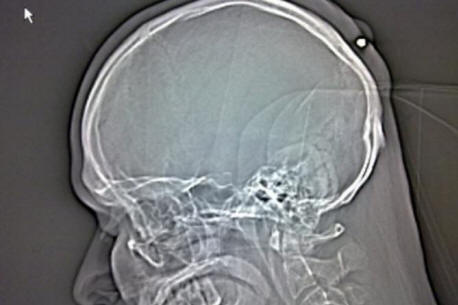

Pri napotitvi na bolnišnico je Autullo temu zavrnil zdravniki so mu pokazali: na rentgenu je bilo jasno, da osem centimetrski železni žebelj se je zataknil tik v lobanji škatle Dante. Preden je rešilca odpeljala Autullo na drugo kliniko operacije, Dante je fotografijo tega objavil na svoji Facebook strani rentgenska slika.